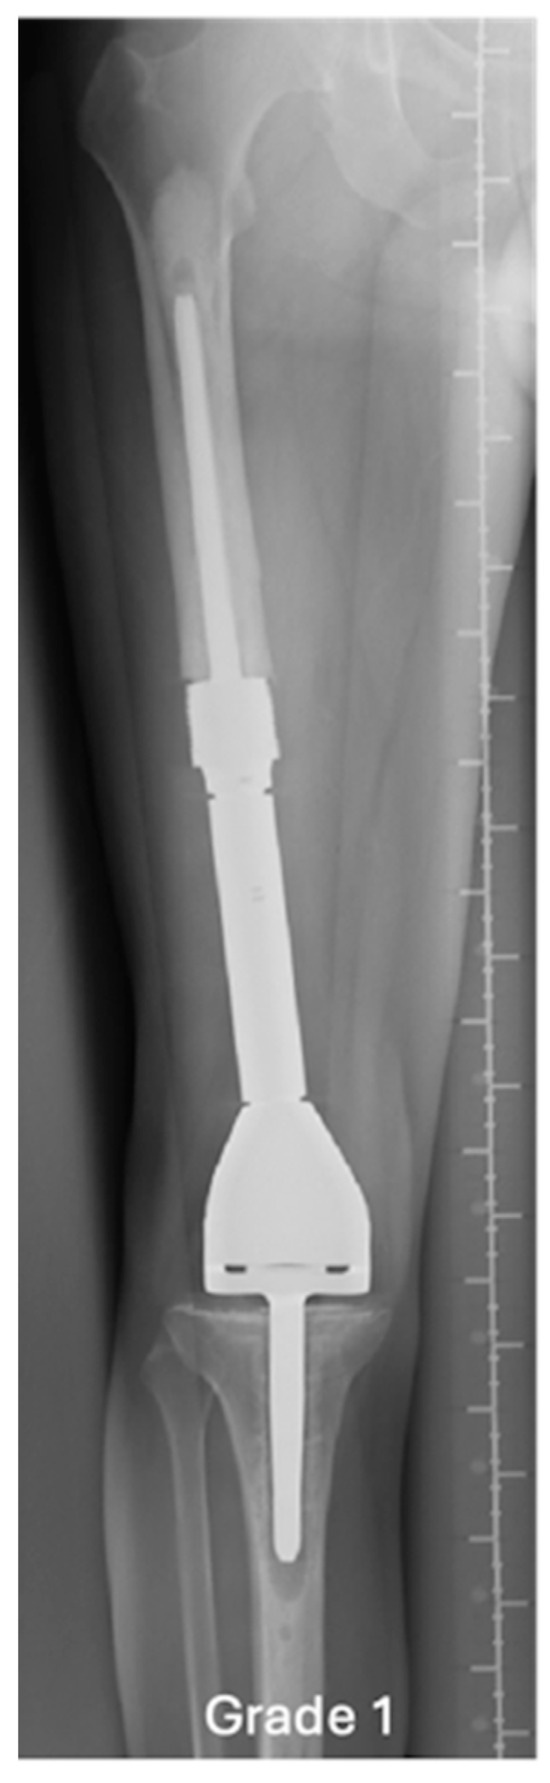

| Grade of loosening | |

| Grade 2 | 5 (17.9) |